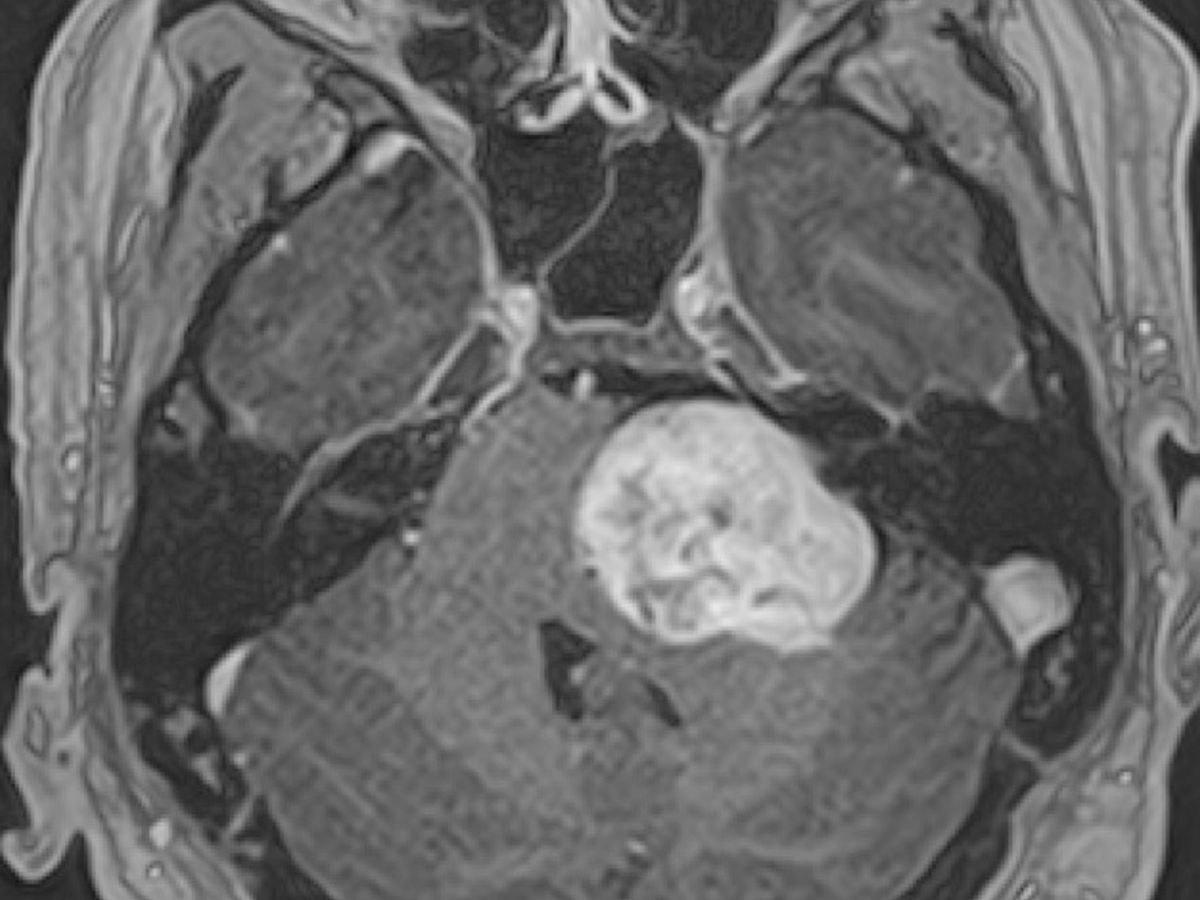

The type of tumor he has is Vestibular Schwannoma which is benign. The size of it is 4x3x3cm

He has sent his MRIs out to a few hospitals around the country and received a call from the best in the country, Dr. Friedman at University of California San Diego. At first Travis was not sure if he would be able to get in with this program because it’s a long wait. Dr. Friedman wants to operate on April 11th.